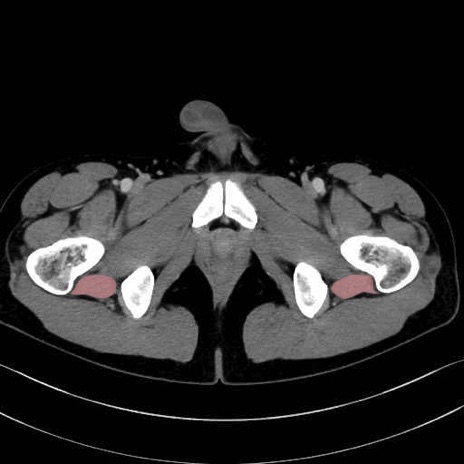

大腿方形筋 (Quadratus femoris)